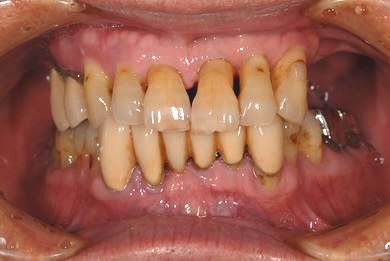

| 性別/年齢 | 男性 / 67歳 | ||||||||||||||||||||||||||||||||

| 主訴 | 欠損部分のインプラント・差し歯治療を希望。 | ||||||||||||||||||||||||||||||||

| 治療内容 | インプラント8本(サイナスリフト、ソケットリフト、GBR)、メタルボンドセラミック8本 | ||||||||||||||||||||||||||||||||

| 治療期間 | 1年5ヶ月 |